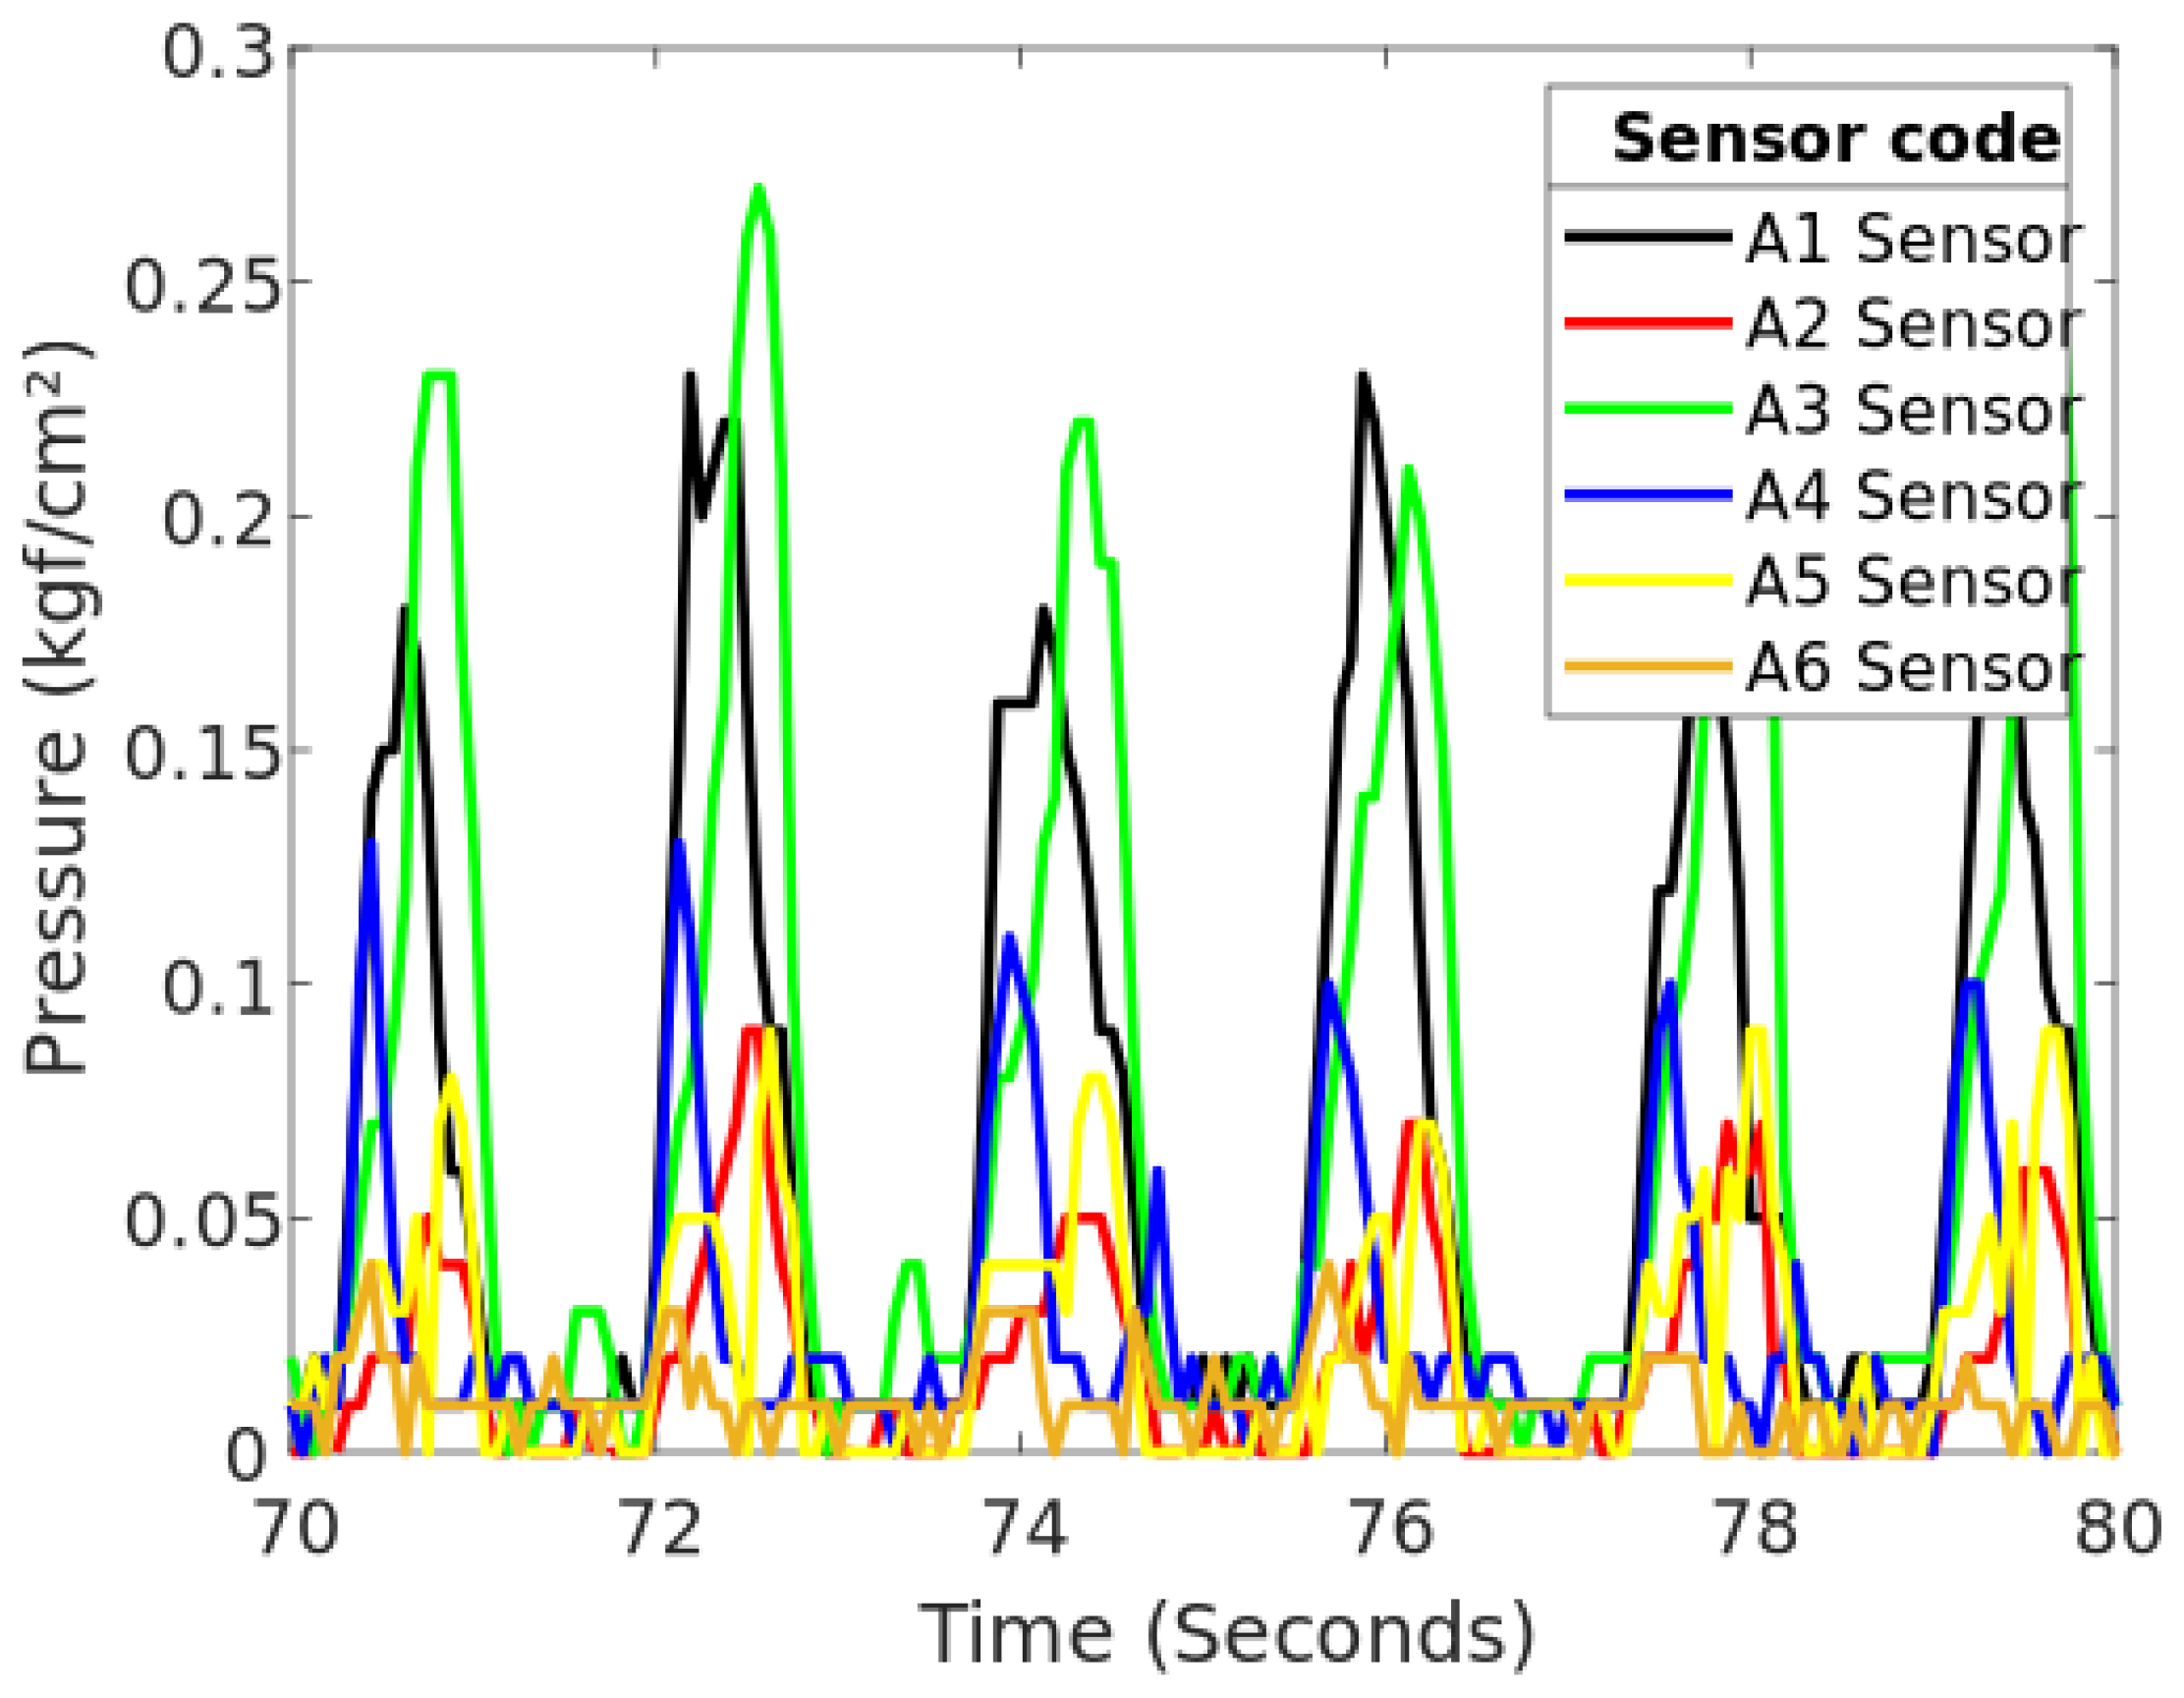

3.3. SIFP System Test